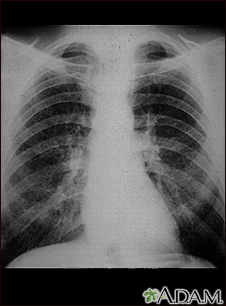

Coal worker's lungs - chest x-rayBackCoal worker's lungs - chest x-rayThis chest x-ray shows coal worker's lungs. There are diffuse, small, light areas on both sides (1 to 3 mm) in all parts of the lungs. Diseases that may result in an x-ray like this include: simple coal workers pneumoconiosis (CWP) - stage I, simple silicosis, miliary tuberculosis, histiocytosis X (eosinophilic granuloma), and other diffuse infiltrate pulmonary diseases. E-mail FormEmail ResultsName:Email address:Recipients Name:Recipients address:Message: